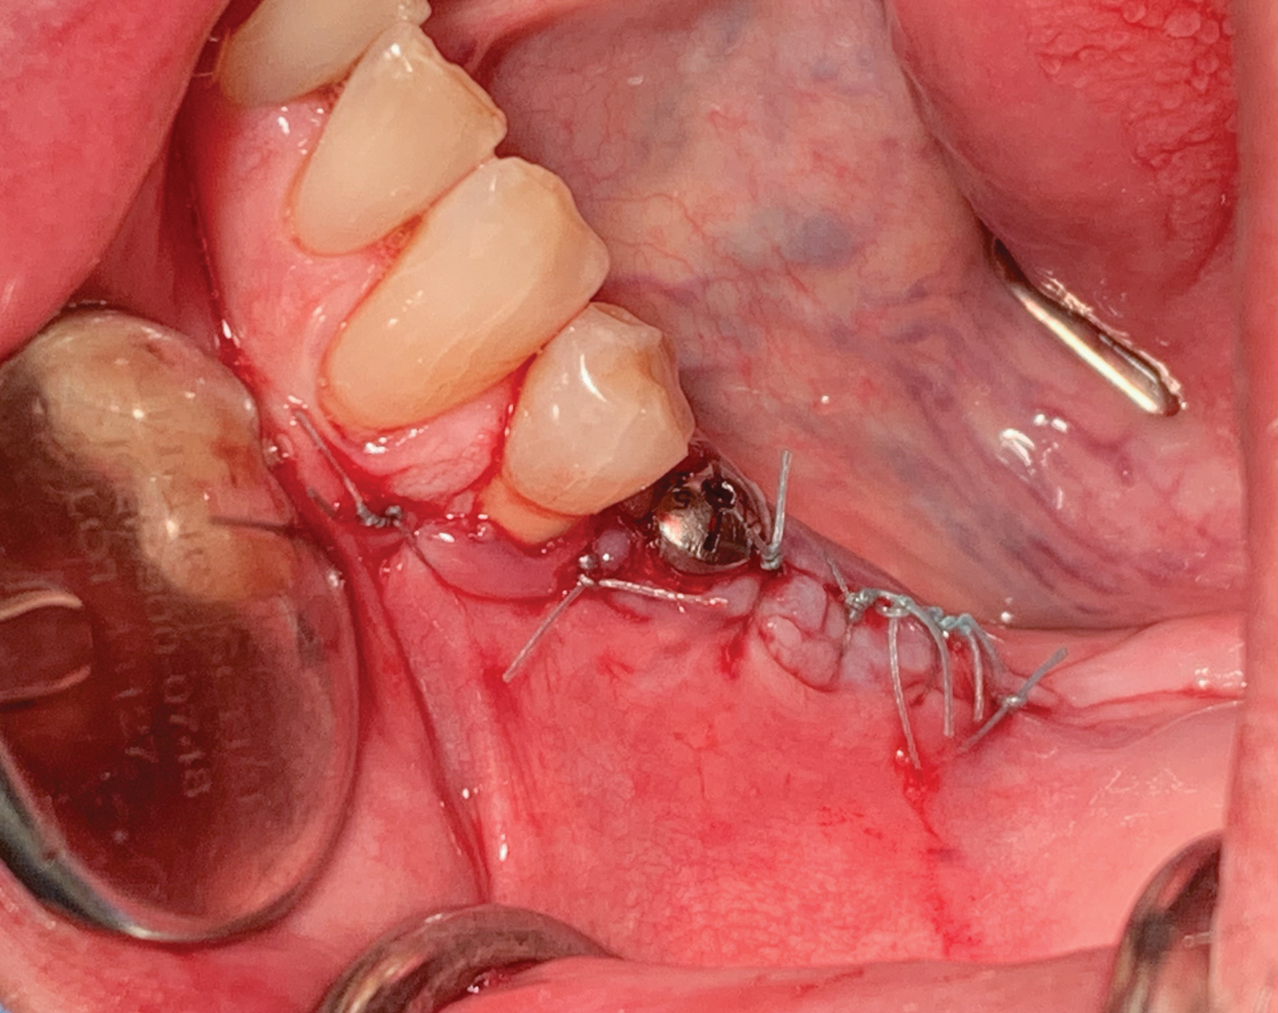

Fig 3. Premolar extracted and flap release.

Figure 3

The patient received amoxicillin 500 mg 3 times a day for 10 days, starting the day before surgery.13,14 A full-thickness flap was elevated, extending from tooth No. 22 to at least one tooth mesial and distal to the mesh placement area (Figure 3). Although a vertical releasing incision was not necessary mesially, one can be made to allow sufficient tissue and ensure tension-free closure. It is important that the vertical incision does not end at the joint between the host bone and mesh. The periosteum in this case was left intact and no superficial release of the mylohyoid lingual was necessary.3,15,16

Tooth No. 20 was extracted atraumatically and the extraction site was thoroughly degranulated. An implant with platform-switching (10 mm length) was placed directly in the extraction socket. The socket was filled with particulate allograft, which was also used to fill the mesh. The receptor site was perforated with a 1.1-mm diameter round bur, but not at the places where the fixation screws would need to be placed.

After implant placement, the mesh was secured in place. Special care was taken to ensure that pre-designed fixation holes did not align with anatomical sensitive areas. The mesh was loaded with the grafting material and placed over the implant. It was fixated with two screws (1.2 mm x 6 mm) designed within the mesh, as planned (Figure 4).

A pericardium membrane was placed. It covered the entire site and extended 2 mm to 3 mm from the mesh margins so it could be secured with tacks and sutures at both the oral and labial surfaces. The membrane was placed under tension to completely cover the grafted site. The flap was advanced and sutured without tension using simple interrupted sutures (Figure 5). At least 6 to 8 months would be allowed for healing to occur.17 A premature loading was avoided; therefore, no interim prosthesis over the grafted site was used.